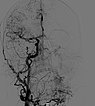

Lateral view of a digital subtraction angiography after contrast injection into the left external carotid artery. The AVM is visible as a diffuse, reticular net-like nidus with direct, strong venous outflow centrally in the left cheek (fast-flow malformation).

Lateral view, DSA after contrast injection in the left internal carotid artery. There is also a massive supply to the nidus of the AVM from the internal carotid artery, mainly via the ophthalmic artery and the meningohypophyseal trunk.

This complicates embolization therapy considerably.

DSA, anterior-posterior view, after injection into the right common carotid artery. The nidus of the AVM on the left cheek is also supplied from the contralateral right external carotid artery and right facial artery.